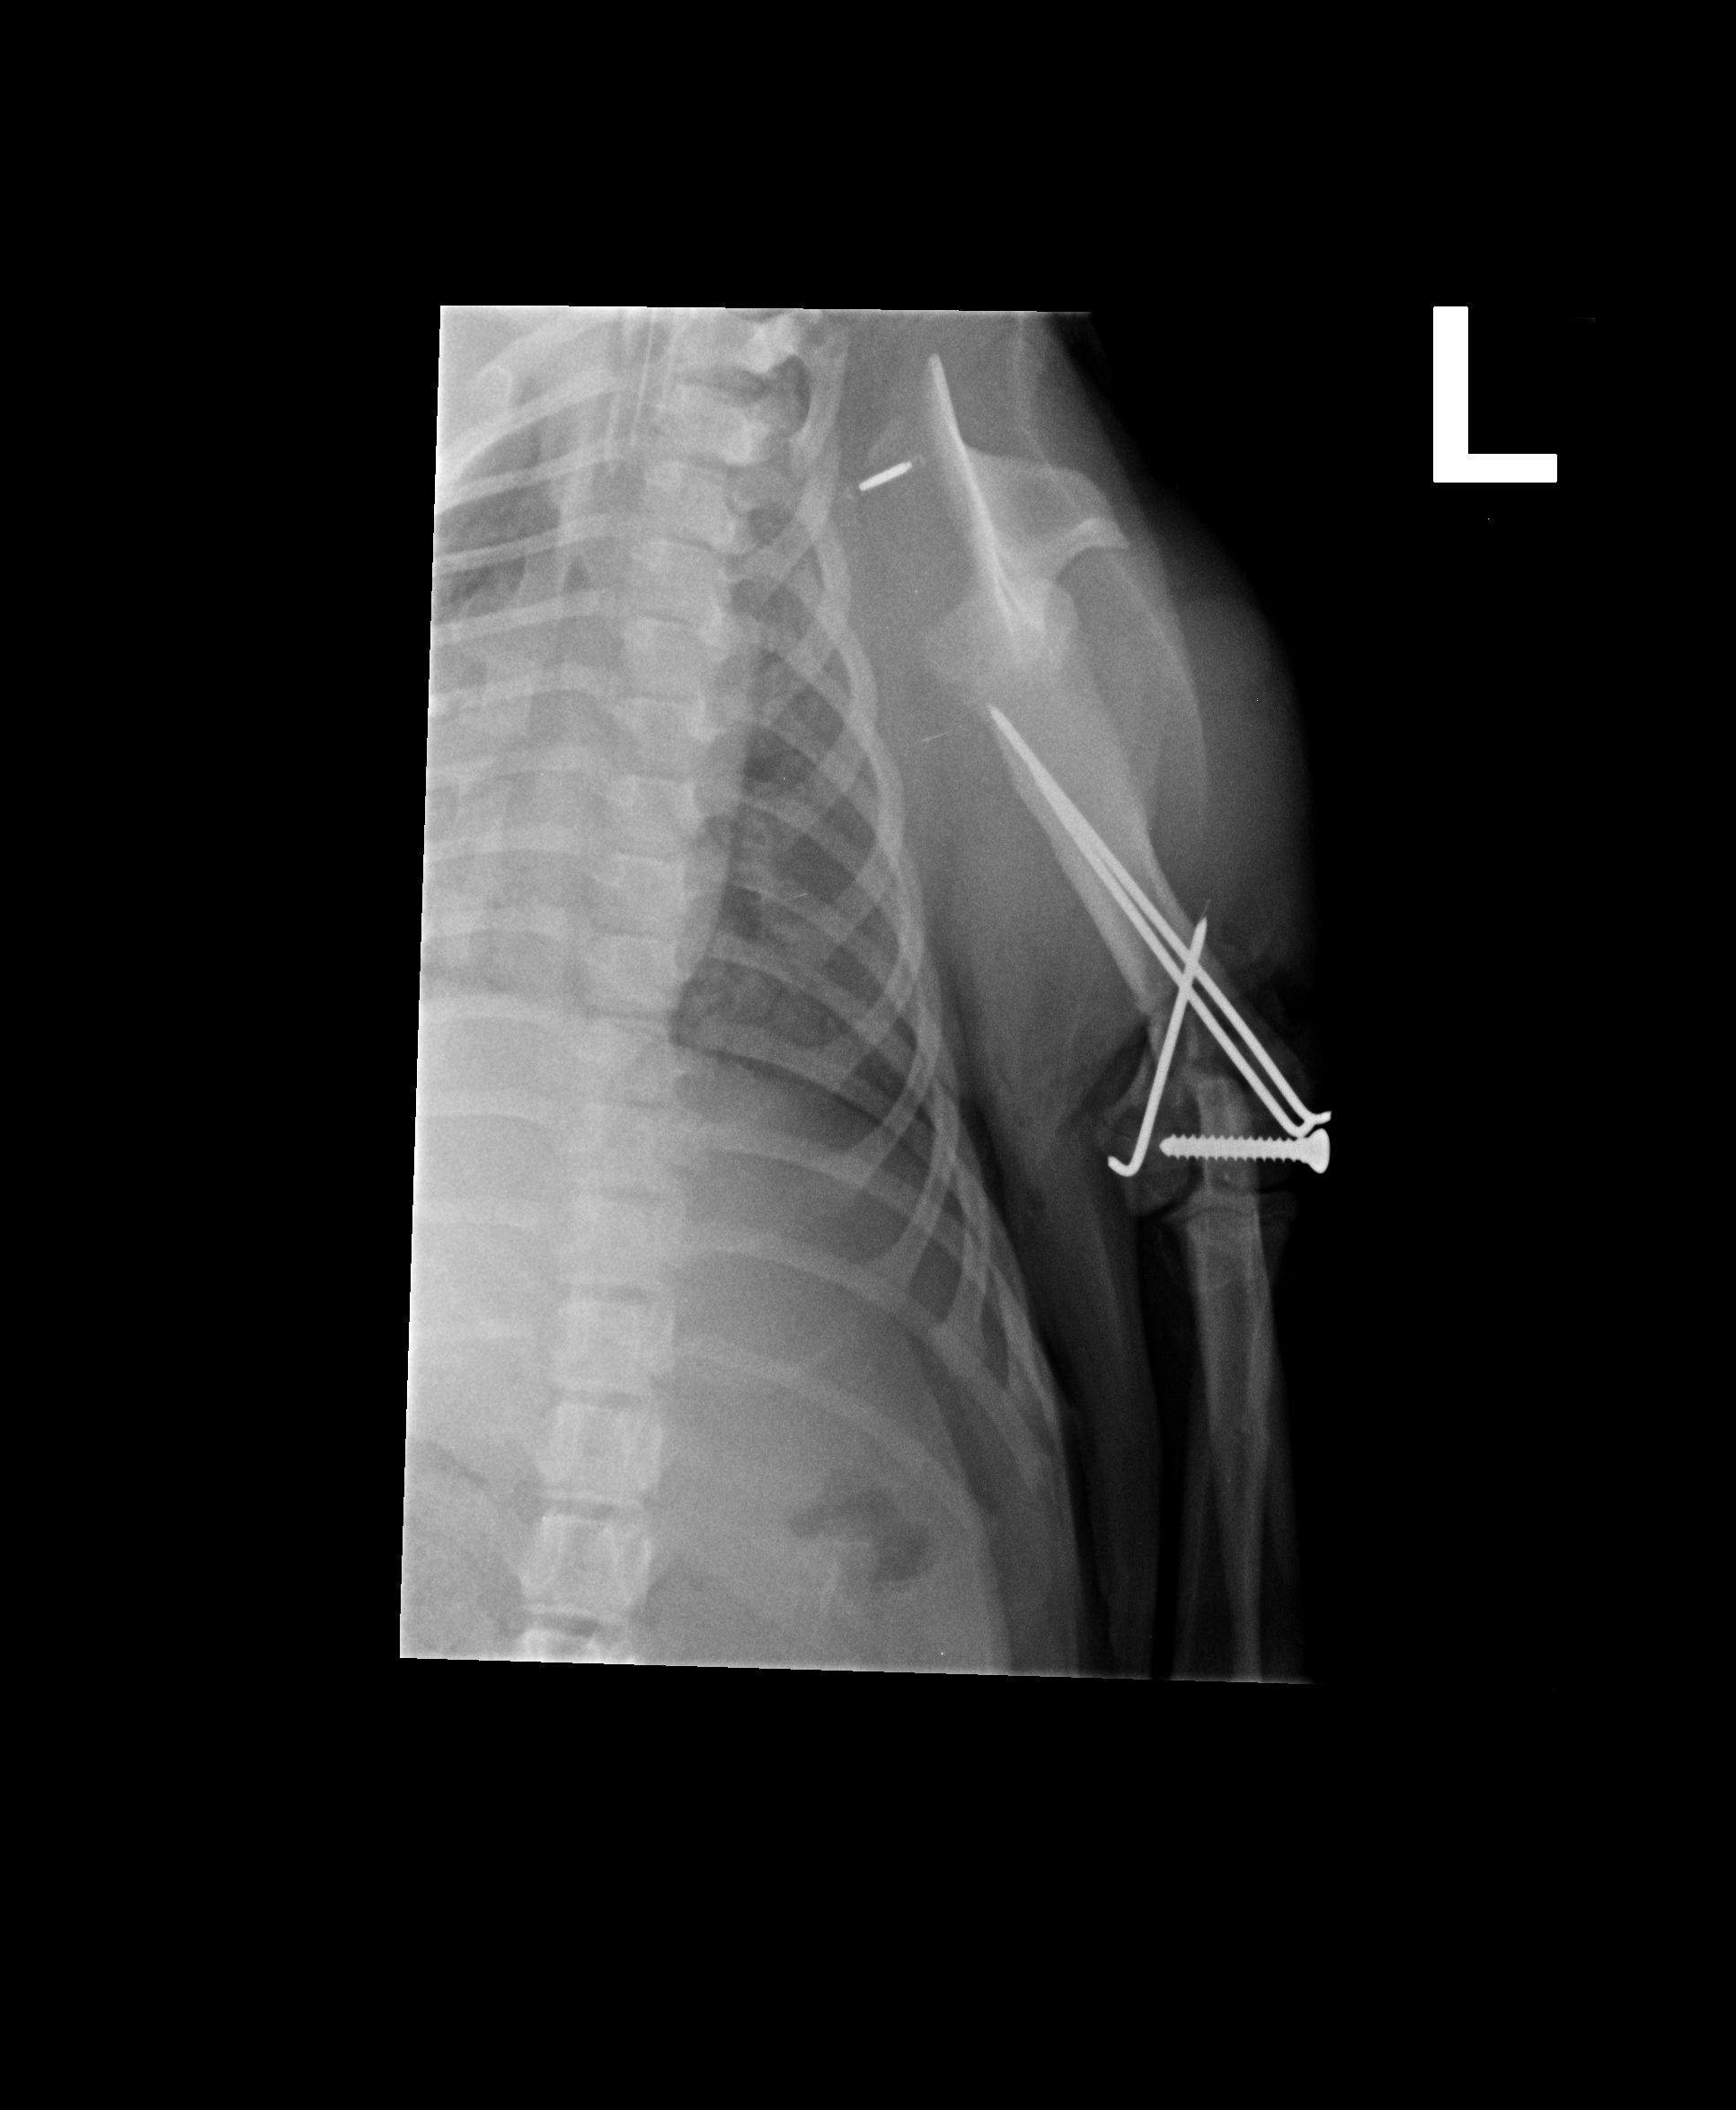

Purpley Posted June 28, 2012 Author Share Posted June 28, 2012 Hey there, She went really well. She had her stitches out yesterday too. She is winging a little (throwing her leg out to walk) which we are hoping will come good once she has recovered a little more. Got the ok to start the underwater treadmill too, and can have 5 mins walks on lead. She is so funny, I take her outside on lead to go to the toilet and she does her toileting and then tries to do the bolt. I think she is secretly hoping that one day that lead won't be attached. When she get to the end of the lead she throws a tantrum and plays dead and I have to go and pick her up. Funny girl. I have attached her post op xray, and am just trying to resize the other couple :) Link to comment Share on other sites More sharing options...

Purpley Posted June 28, 2012 Author Share Posted June 28, 2012 The pic the vet sent me after her op Billy and Spirit, day before her op. Waiting to make sure she didn't have any neuro issues. Link to comment Share on other sites More sharing options...